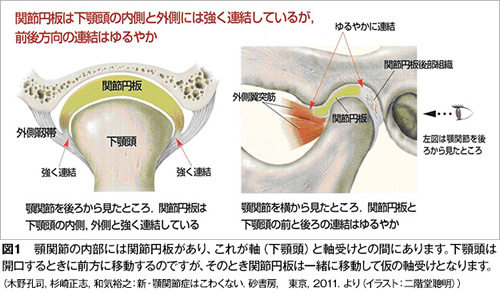

顎関節症の病気の状態(病態)は現在4つに分類されています。最も多いのは関節内にある関節円板(図1)というクッションが前方にずれることで起きる「カクンカクン」という音が出る状態(図2)、あるいはずれがもっと大きくなることで大きな口が開けられなくなる状態です(図3)。